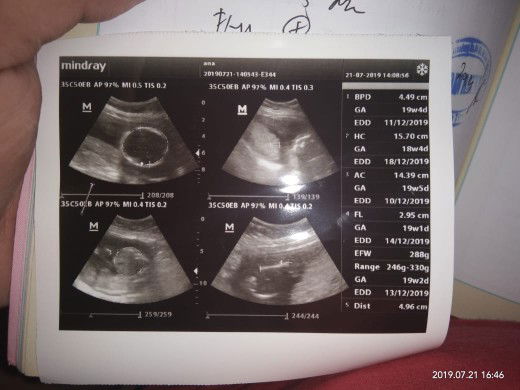

USG

Alhamdulilah sehat sehat terus ya sayang, dan ga sabar pengen tau jenis kelaminnya. Tapi mau Perempuan ataupun laki2 minta sehat dan tidak kurang satu apapun??